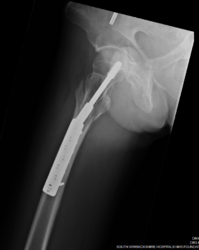

I still have problems standing on the bad leg. Two legs is fine, but for example putting on shoes and putting most of my weight through the bad leg gives me pain when the weight is released. Stairs are also a problem with the bad leg. - Can get pain through my buttock unless I twist my leg. Stops me from standing on the bike pedals for the same reason. Because of this, last time I saw the consultant he said he would discuss with me in August about removing the metal work.